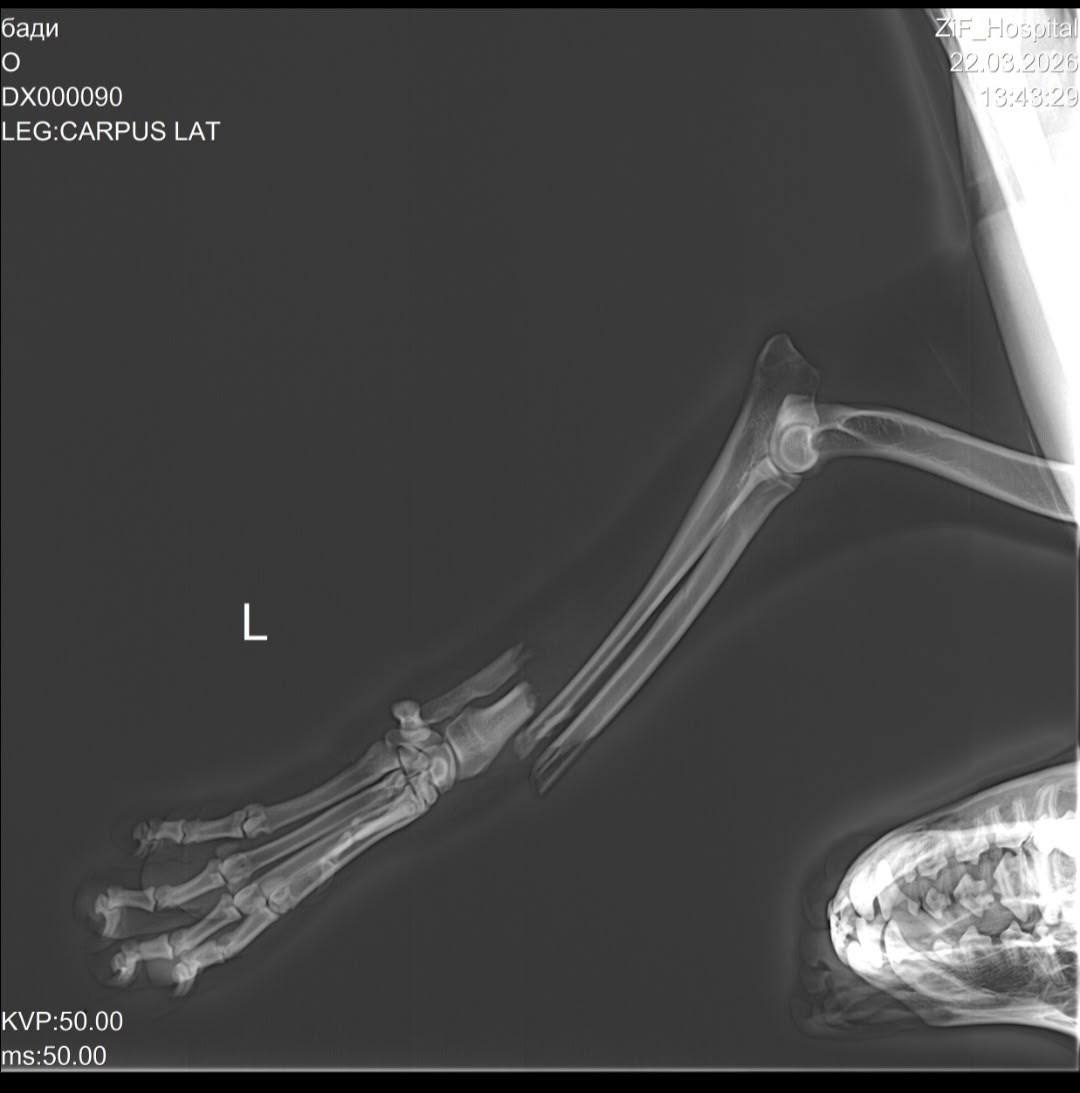

Как рассказали очевидцы, машина переехала Бадди переднюю лапу — кость торчала наружу. Собаку отнесли домой. Хозяйка пса зафиксировала перелом палкой и перемотала бинтом.

Конечность кровоточила, а сам пёс без помощи и обезболивающих пролежал дома четыре дня. Неравнодушные соседи написали о ситуации в соцсетях 21 марта и попросили откликнуться волонтёров. Зоя Шумилова договорилась с клиникой, собаку привезли на осмотр, после чего владелица написала отказ от питомца.